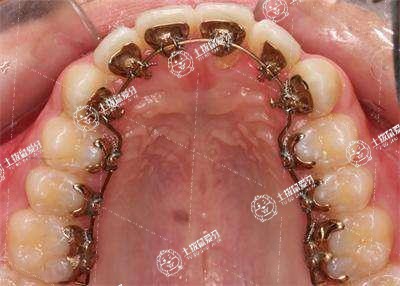

舌側(cè)矯正是通過將矯治器安裝在求美者牙齒的舌側(cè)面來進(jìn)行正畸治療的,就是說在進(jìn)行牙齒矯正時,從外觀上通常是是看不到的。而且這種矯治技術(shù)早在20世紀(jì)70年代就已經(jīng)開始出現(xiàn)了,它可以避免在運動時唇側(cè)矯正器對求美者唇側(cè)的損傷。

舌側(cè)隱形矯正的效果是比較不錯的,這種方法需要把矯治器安裝在牙齒的側(cè)面,通過矯治器傳導(dǎo)的矯治力讓牙齒發(fā)生移位,從而達(dá)到矯正牙齒的目的,這種方法在手術(shù)之后可以取得比較明顯的效果,可是需要長時間堅持。在恢復(fù)期間還要注意做好相應(yīng)的護(hù)理工作,不要吃些過于堅硬或者是辛辣的食物,避免誘發(fā)不良的影響,延長恢復(fù)的時間。

舌側(cè)矯正一般需要兩三年。牙齒的矯正需要非常長的時間,一般需要兩三年的時間。舌側(cè)矯正的器具可以完全貼合牙齒,并且特別隱形,假若病人考慮美觀的話可以進(jìn)行舌側(cè)矯正。而且舌側(cè)矯正不會損傷牙齒表面的牙釉質(zhì),能減弱患蛀牙的風(fēng)險。需要注意的是,舌側(cè)矯正的器具是安裝在舌側(cè)的,所以容易造成病人的不適,而且會對病人的發(fā)音有一定影響。

舌側(cè)矯正是通過設(shè)計,精密鑄造托槽,完成弓絲的準(zhǔn)確成型。舌側(cè)矯正,避免鋼絲矯正佩戴牙套對美觀的影響。平??梢运绍涱惡土魇碁橹鳎瑴p少舌頭的活動量,避免舌頭頻繁活動引起校準(zhǔn)失敗。